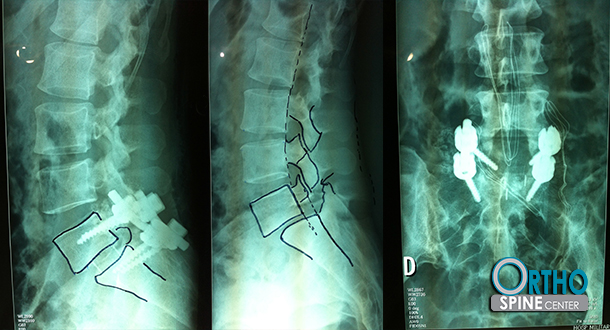

Diagnostico espondilolistesis l5-s1

Grado 1.